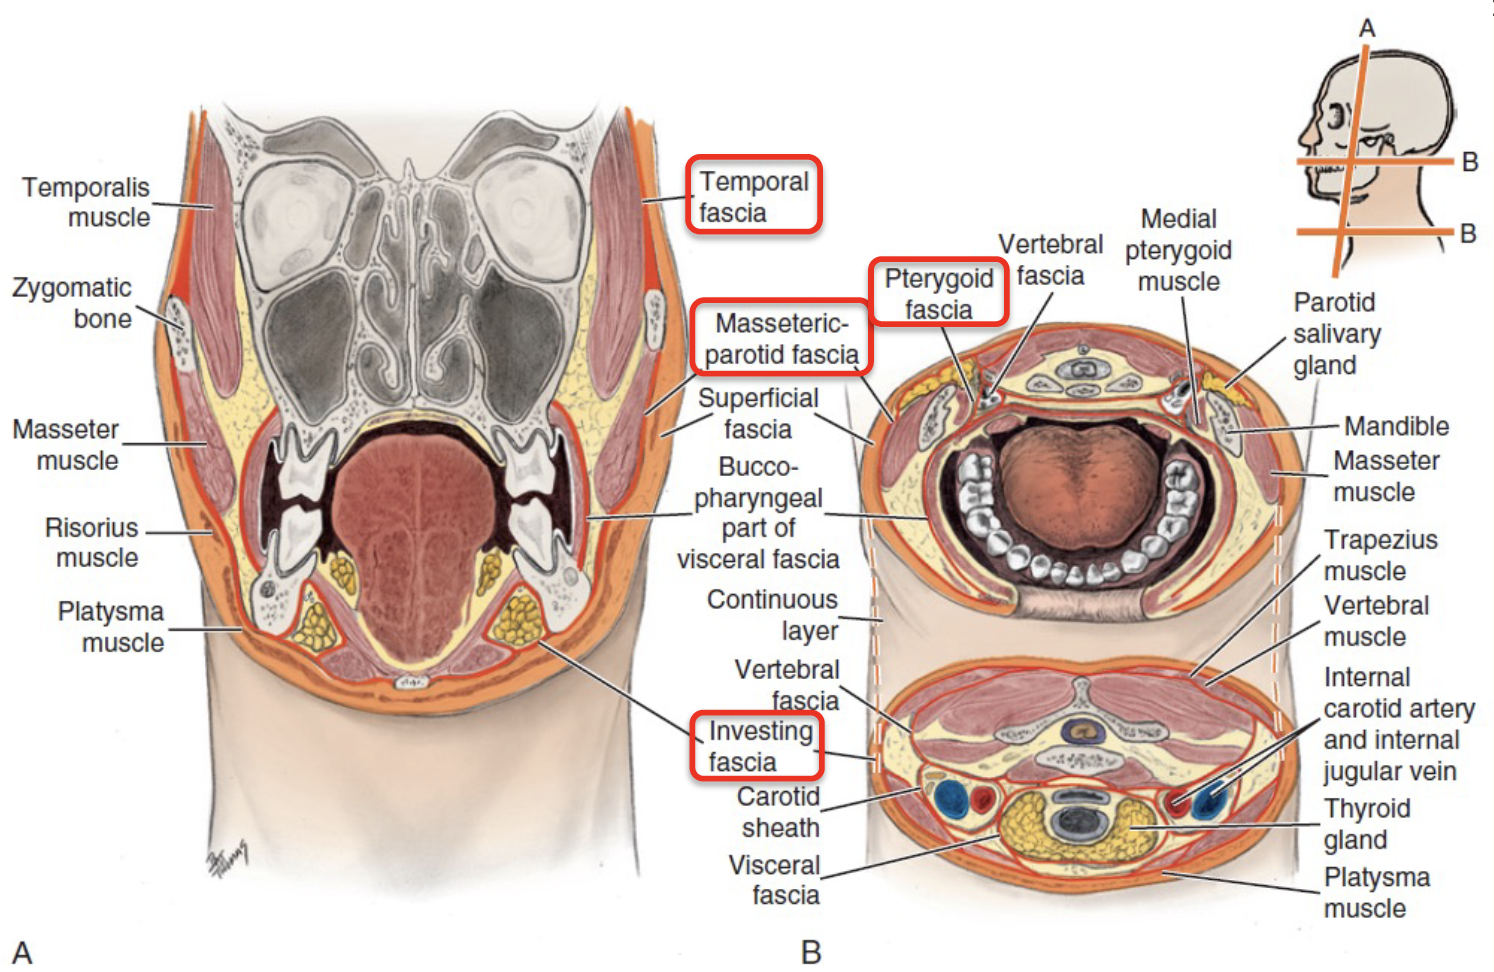

Fasciae

Superficial fascia

- 表情肌

Deep fascia

Head

- Temporal fascia

- Temporal arch以上

- Masseteric-parotid fascia

- Temporal arch以上

- 連到investing fascia

- Buccopharyngeal fascial

- 連到investing fascia

- Pterygoid fascia

- Pterygoid m. 外

Neck

-

Investing fascia

- 最外層

-

Carotid fascia

-

Visceral fascia

- 食道呼吸道

-

Vertebral facial